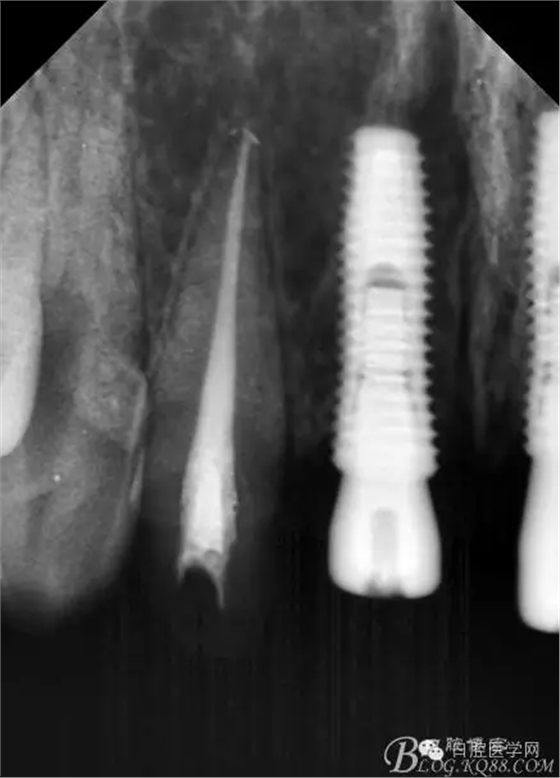

設(shè)計(jì)方案:11.21種植(選用登騰系統(tǒng),GBR植骨)12.22 RCT后樁冠修復(fù),牙齦瓷修復(fù)。

一期手術(shù)后3-6個(gè)月可做二次修復(fù),接愈合基臺(tái),拆線后10-15天根據(jù)情況可以采模型做牙冠。